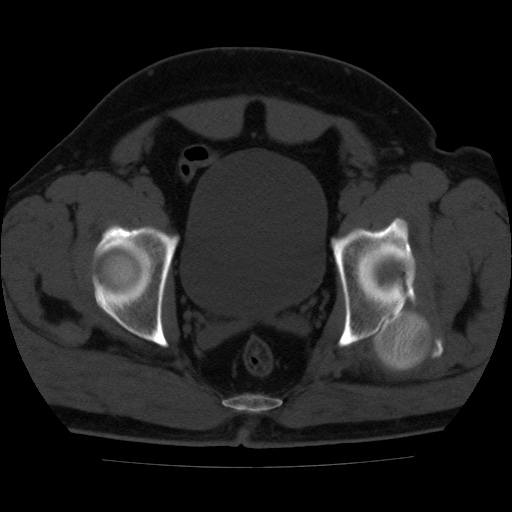

标题: CT21643:男,42岁,车祸伤后左髋关节疼痛剧烈1小时。 [打印本页]

男,42岁,车祸伤后左髋关节疼痛剧烈1小时。

左髋关节脱位并髋臼骨折,左髋关节积血。

左髋关节后脱位并髋臼骨折,左髋关节积血

左髋关节后脱位,大小转子皮质撕脱骨折,关节腔“脂血症”,左侧盆底少量积血,左侧髋臼邻关节囊肿。

左髋关节后脱位并髋臼骨折、股骨头前方骨折,左髋关节积血 。

左髋关节(股骨头)后脱位,并髋臼及股骨头骨折,左髋关节积血。

左髋关节后脱位并髋臼后缘骨折、股骨头前方骨折,左髋关节积血 。我遇到过一例。